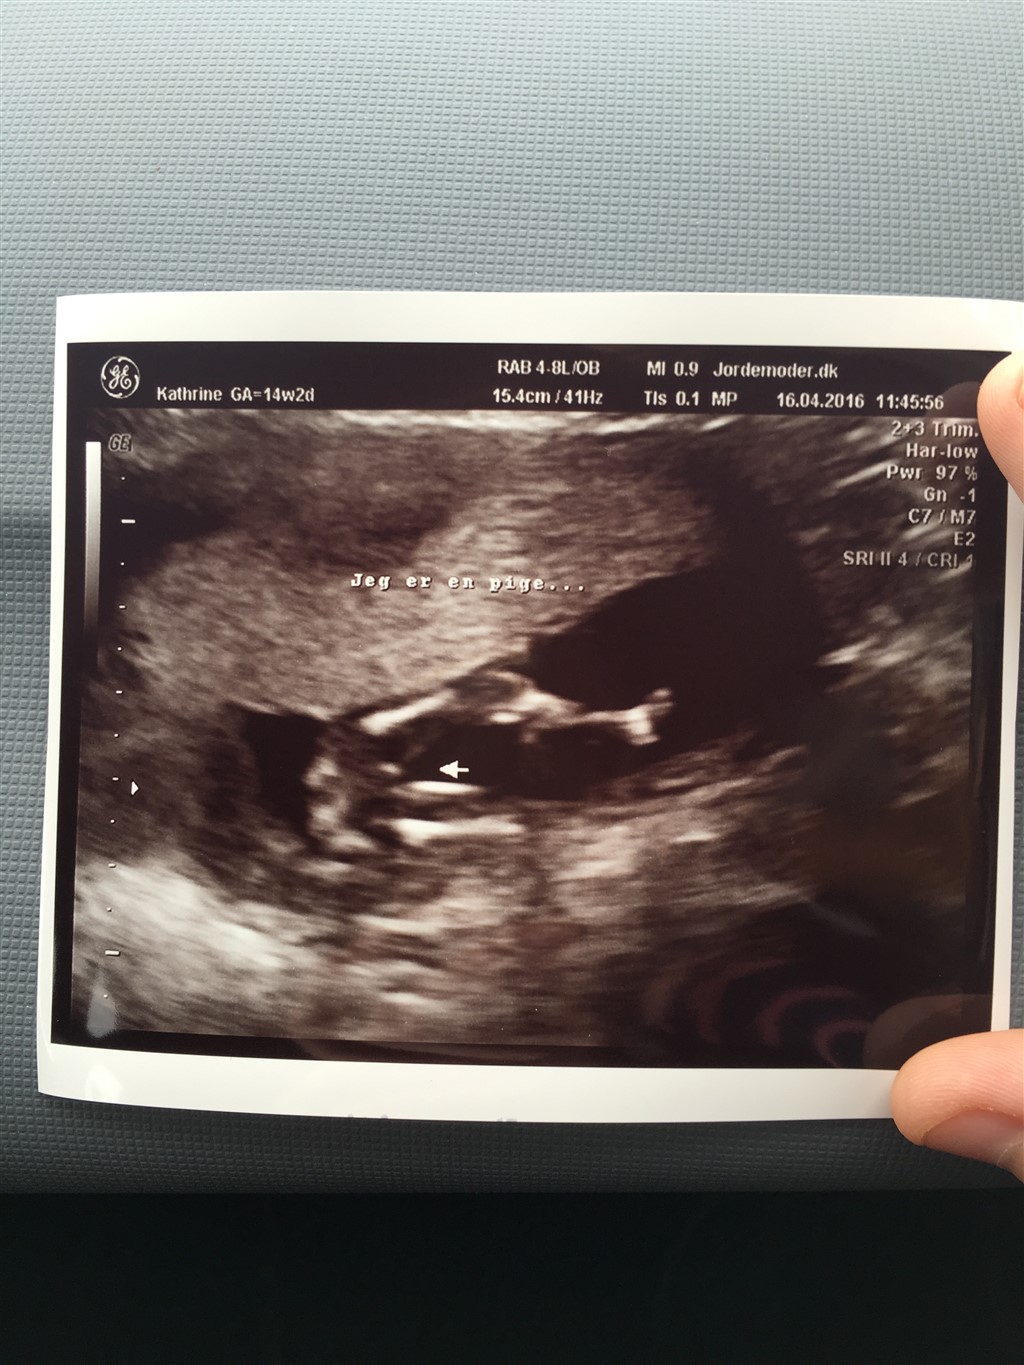

Det er sørme en pige

vi var til kønsscanning i dag og det er sørme en lille pige, der gemmer sig i hulen